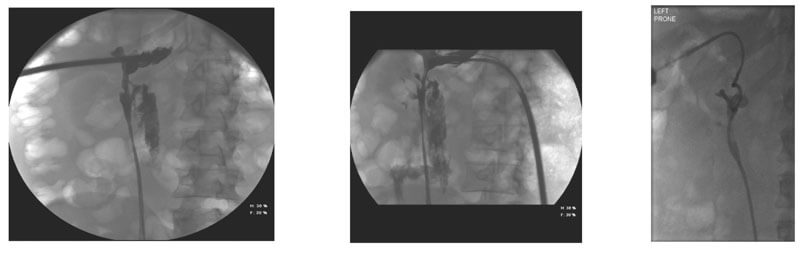

Whilst initially it might be reassuring, the absence of any blood-stained urine in the urethral catheter may indicate ipsilateral ureteric obstruction (either from a stone fragment, ureteric oedema or a blood clot) as the clear urine seen in the bladder represents normal urine from the contralateral kidney. Within this scenario, persistent and worsening haematuria through the nephrostomy is an indicator of clot-colic, for which additional vigilance for bleeding is needed. In any of these situations, imaging (by CT KUB, nephrostogram or CT angiogram as appropriate) will identify the level and cause of obstruction and allow onward management as required, including the opportunity to deploy an antegrade stent via the nephrostomy tract (Figure 3).

Figure 3: Pain on clamping nephrostomy with ensuing extravasation secondary

to distal obstruction followed by interval nephrostogram after antegrade stent.